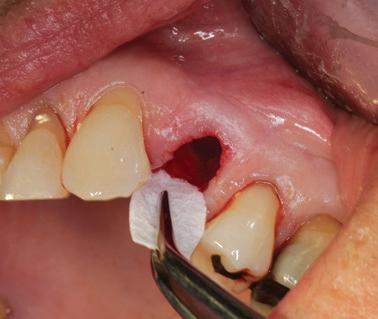

La gestion de l’alvéole post-extraction constitue un défi fréquent en pratique clinique. Lorsqu’un traitement implantaire est envisagé, le contrôle de la résorption osseuse verticale et horizontale devient essentiel afin de préserver les conditions idéales pour un futur positionnement implantaire.

L’objectif de ce module est de permettre une approche rigoureuse de la préservation alvéolaire, en vue d’optimiser le positionnement tridimensionnel de l’implant et de faciliter l’intégration fonctionnelle et esthétique de la restauration prothétique.

Maîtriser les techniques d’extraction atraumatique

Utiliser efficacement les outils diagnostiques (photographie, imagerie, etc.)

Comprendre les objectifs et indications de la préservation alvéolaire

Sélectionner les biomatériaux appropriés (substituts osseux, membranes) et les techniques de suture

Évaluer les indications de temporisation et choisir la solution adaptée

Pratiquer les techniques de préservation alvéolaire en atelier